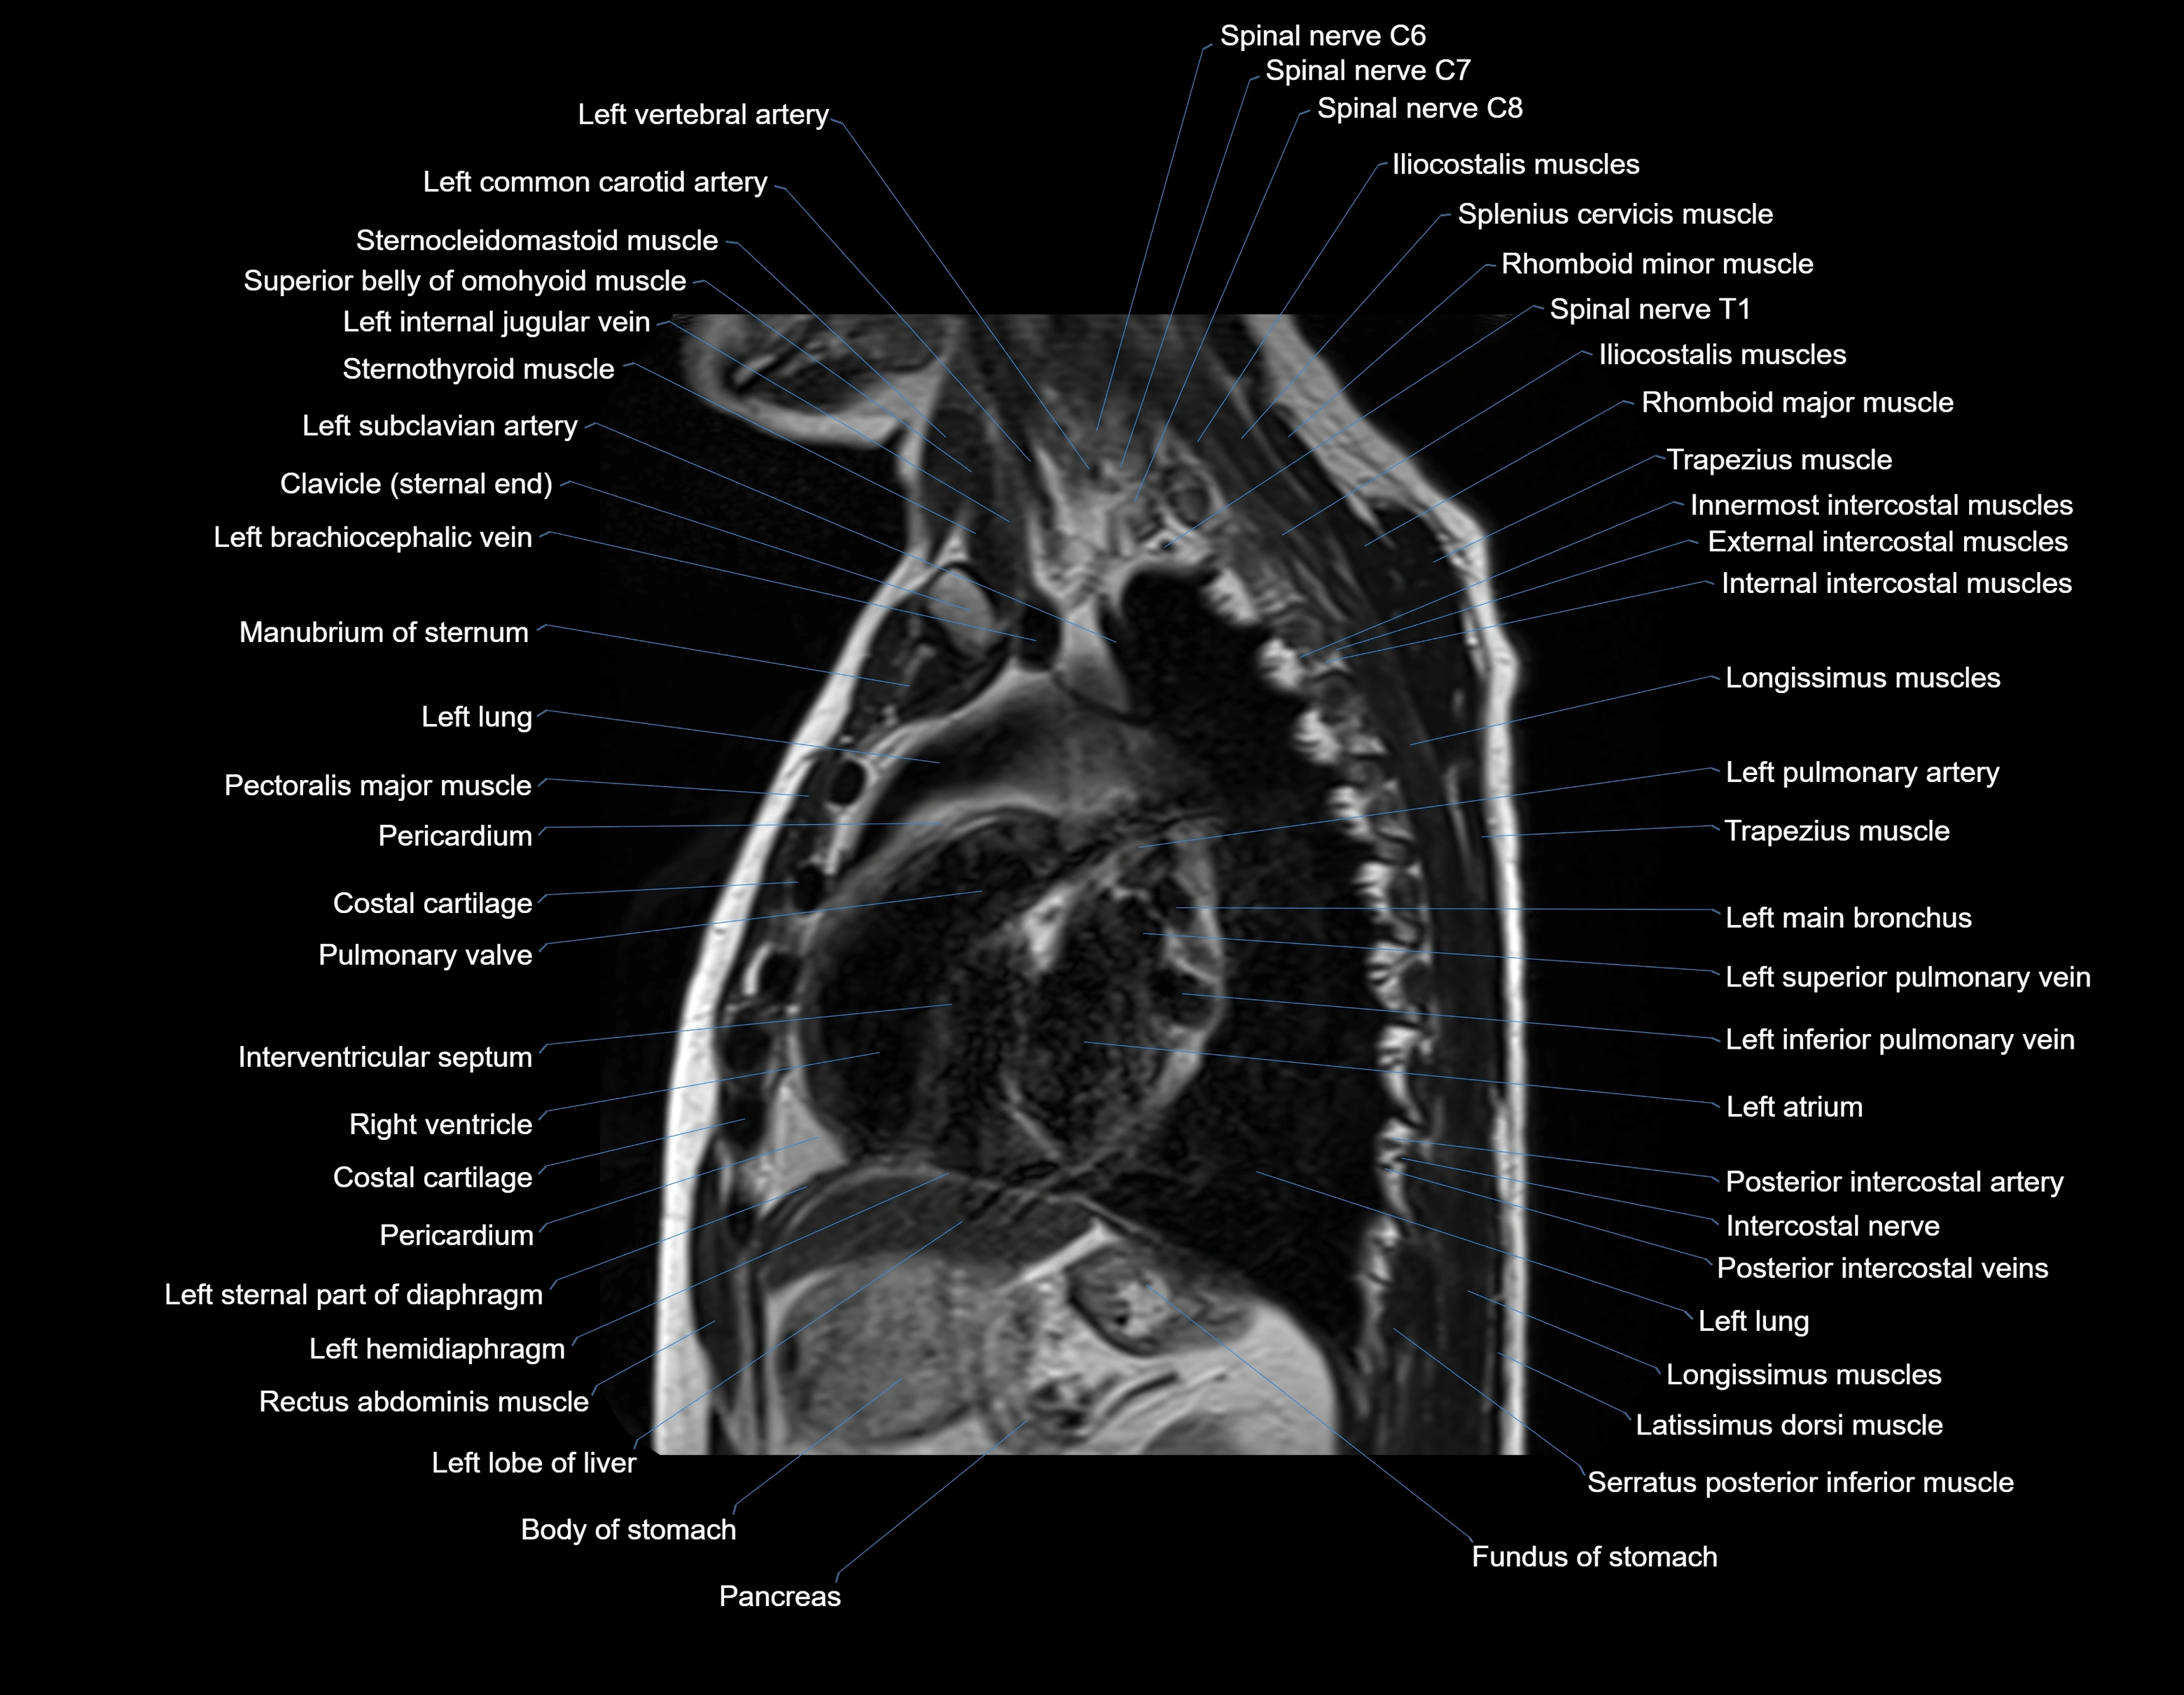

MRI images